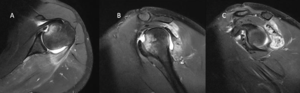

Magnetic Resonance Arthrogram (MRA)

Contrast enhancement during magnetic resonance arthrogram (MRA) is of great value and will increase the sensitivity of magnetic resonance imaging (MRI) in identifying a soft tissue injury (cartilage, rotator cuff, labral tears (Figure), a patulous capsule (Figure), reverse humeral avulsion of the glenohumeral ligaments (rHAGL, Figure), associated findings such as paralabral cysts) (Figure).